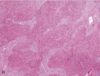

What is seen here?

• Key features?

Primary Biliary Cirrhosis

• Destruction of intrahepatic bile ducts (small and medium)

• Notice lymphocytic infiltration near the biliary tract